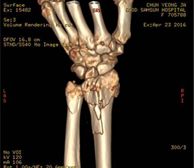

1. 분야별 전문 과장의 특성화 진료 좋은삼선병원 인공관절센터는 고관절, 무릎 관절, 어깨 관절, 수족부 관절 등 질환 부위별 특성화 진료를 통해 맞춤 치료를 시행합니다.

2. 인공관절시술 시행 병원(고관절 / 슬관절 / 견관절)좋은삼선병원 인공관절센터는 고관절, 슬관절, 견관절 등 다양한 인공관절시술을 시행하고 있습니다.